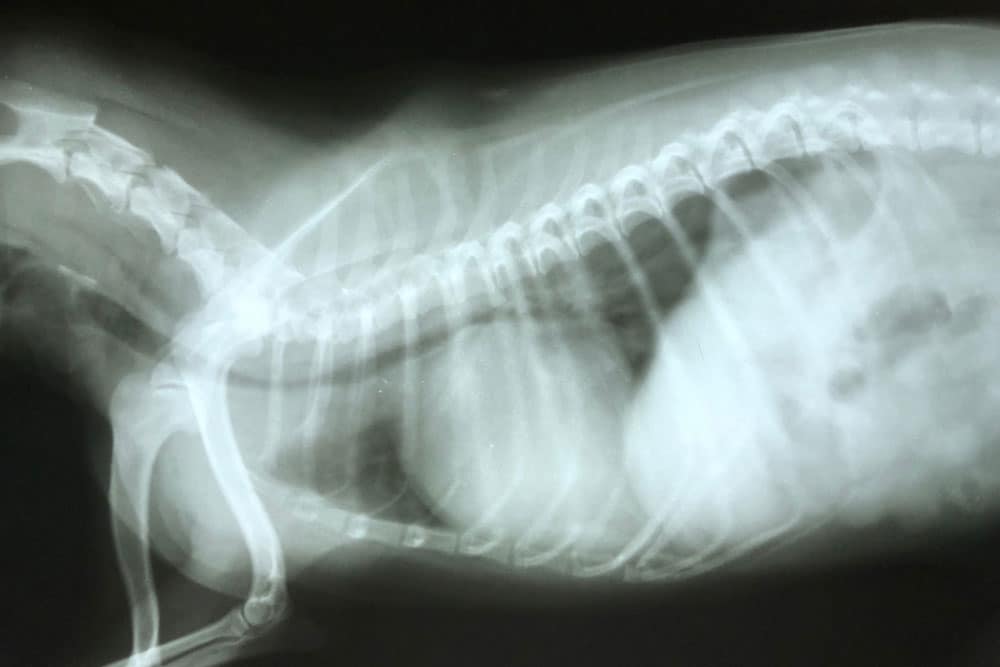

X-rays Coming To You: How Mobile Veterinary Care Helps Pets With Mobility Issues

Safe, Simple, and Stress-Free: X-Rays at Home for Pets in Lewes The salty air, long walks on the beach, watching [...]